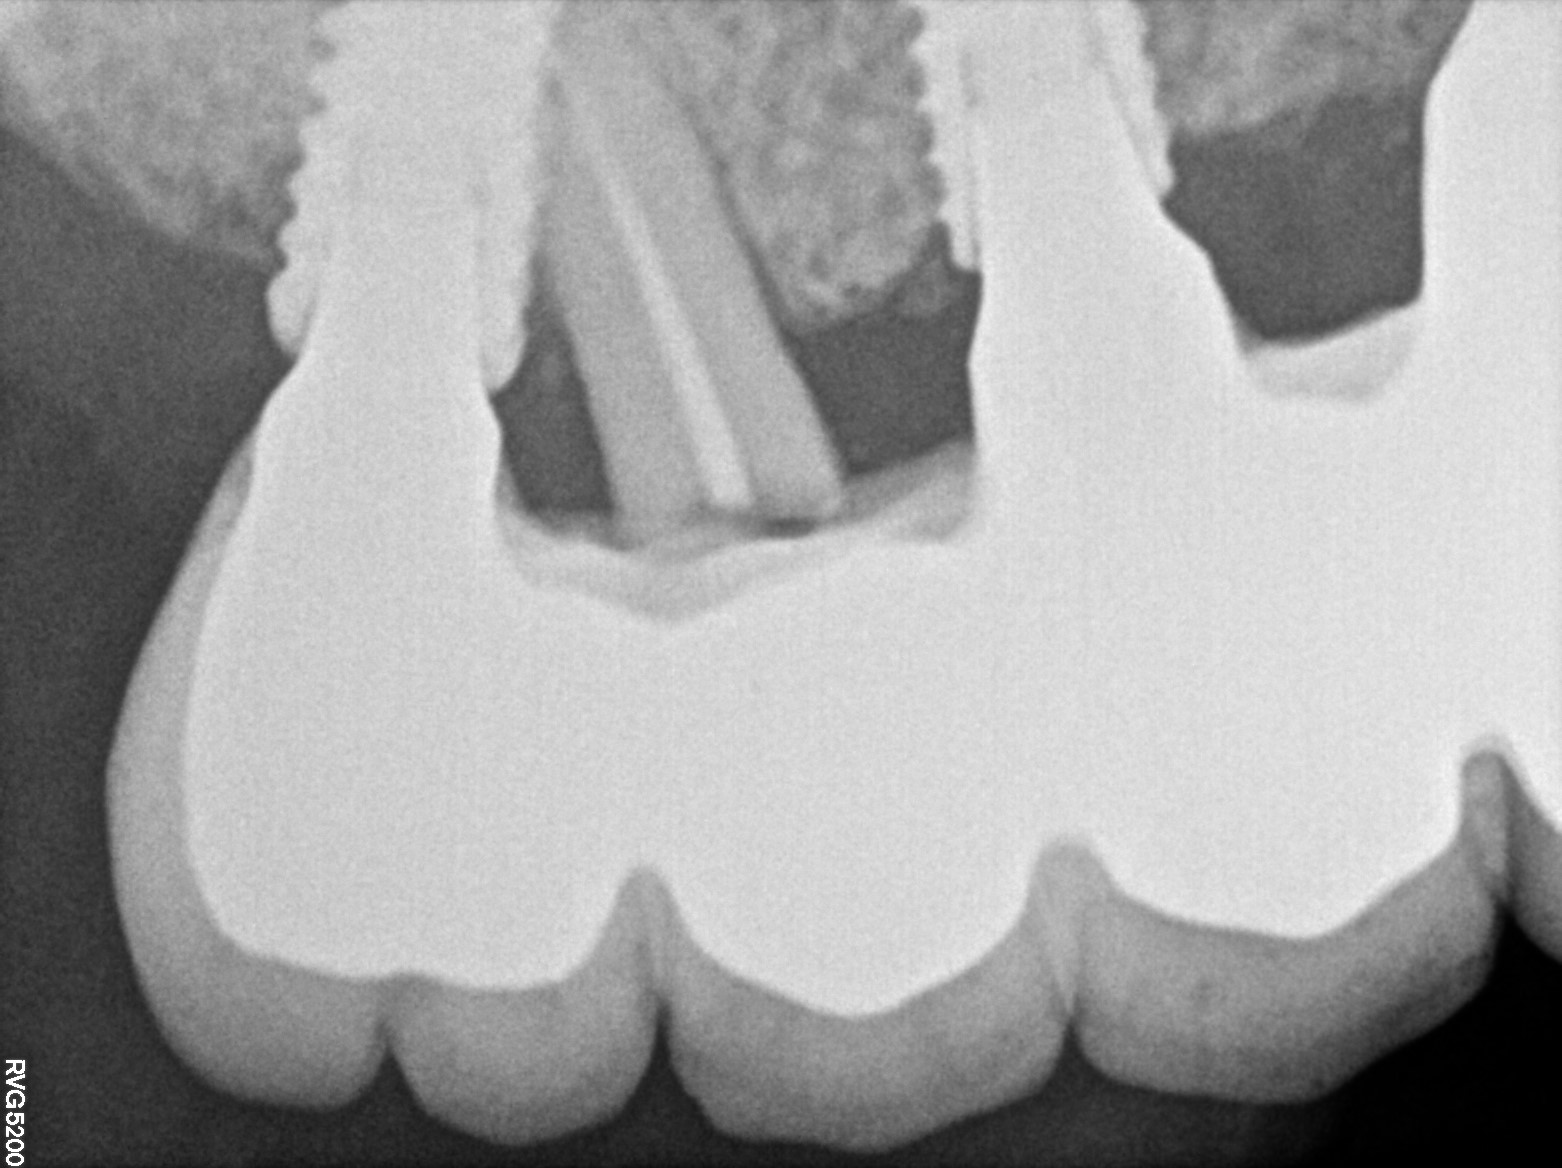

Dental Radiographs FHIR: DocumentReference · LOINC 24641-7

xray_1742374042.jpg

24641-7

| Dental implant placement | 234781005 | D6010 Surgical placement of implant body | — | 2025-03-19 | completed | full mouth implant done @ dr shoebs. came for checkup in 1st and 2nd quad. adv to return if any symptoms | |

| Dental implant placement | 234781005 | D6010 Surgical placement of implant body | — | 2025-03-19 | completed | implant hole filled |